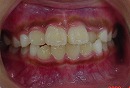

矯正前の写真を見ると、

上の前から2番目の歯だけ咬み合わせが上下逆になっています。

矯正後は、上下の咬み合わせが改善しています。